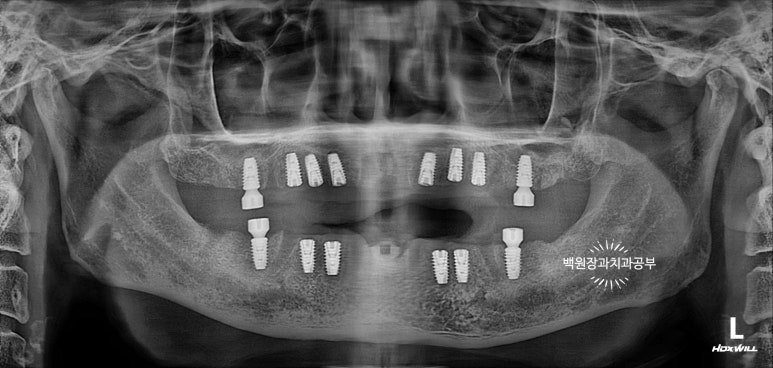

최종 보철물.. 드디어 제작이 되었습니다.

전체 임플란트를 완성하는데 전체 치료기간은 약 8개월 정도 걸렸습니다. 상당히 빨리 졸업하신 편이에요!

정면에서 보시면 임시 치아와 다르게 훨씬 깊이감 있는 색상으로 제작되어 자연스럽고, 완성도 있는 형태를 확인하실 수 있습니다.

그리고 치과용 파노라마로 확인해보시면, 정확한 위치에 정확한 보철물이 제작되어 상당히 조화로운 결과를 확인하실 수 있으실거에요! 치과의사로 살면서 가장 기쁘고 감동적인 순간 중 하나입니다.

정말 너무너무 보람찹니다 :) ㅎㅎ 환자분께서도 굉장히 만족해하셨어요!